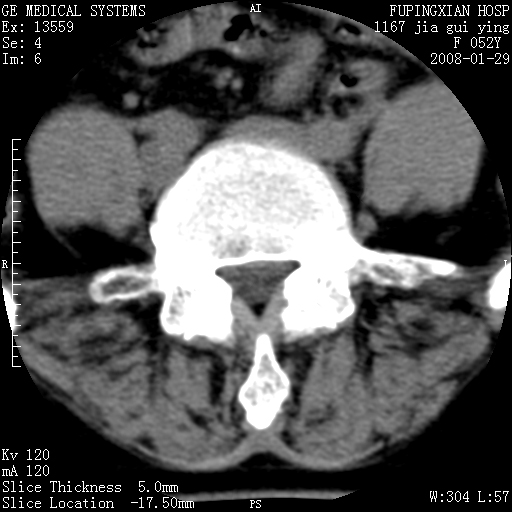

以下是引用zhangzhongshou在2008-1-29 19:34:00的发言:[br]1、腰椎退行性变。[br]2、硬膜囊内钙化,多考虑蛛网膜炎所致粘连钙化

以下是引用dyqct在2008-1-29 21:49:00的发言:[br]考虑:1、腰4-5椎间盘突出(左椎间孔外侧型)。[br] 2、硬膜囊内钙化,多考虑蛛网膜炎所致粘连钙化,请询问病史病人以往做过碘油造影吗?

以下是引用liuyue在2008-1-30 4:32:00的发言:[br]1. 腰4-5椎间盘突出。[br]2. 硬膜囊内钙化,考虑a.蛛网膜炎所致粘连钙化;[br] b.硬膜囊内血管畸形.[br] c脊髓纵裂畸形.[br] 另:询问病史病人以往做过碘油造影吗?